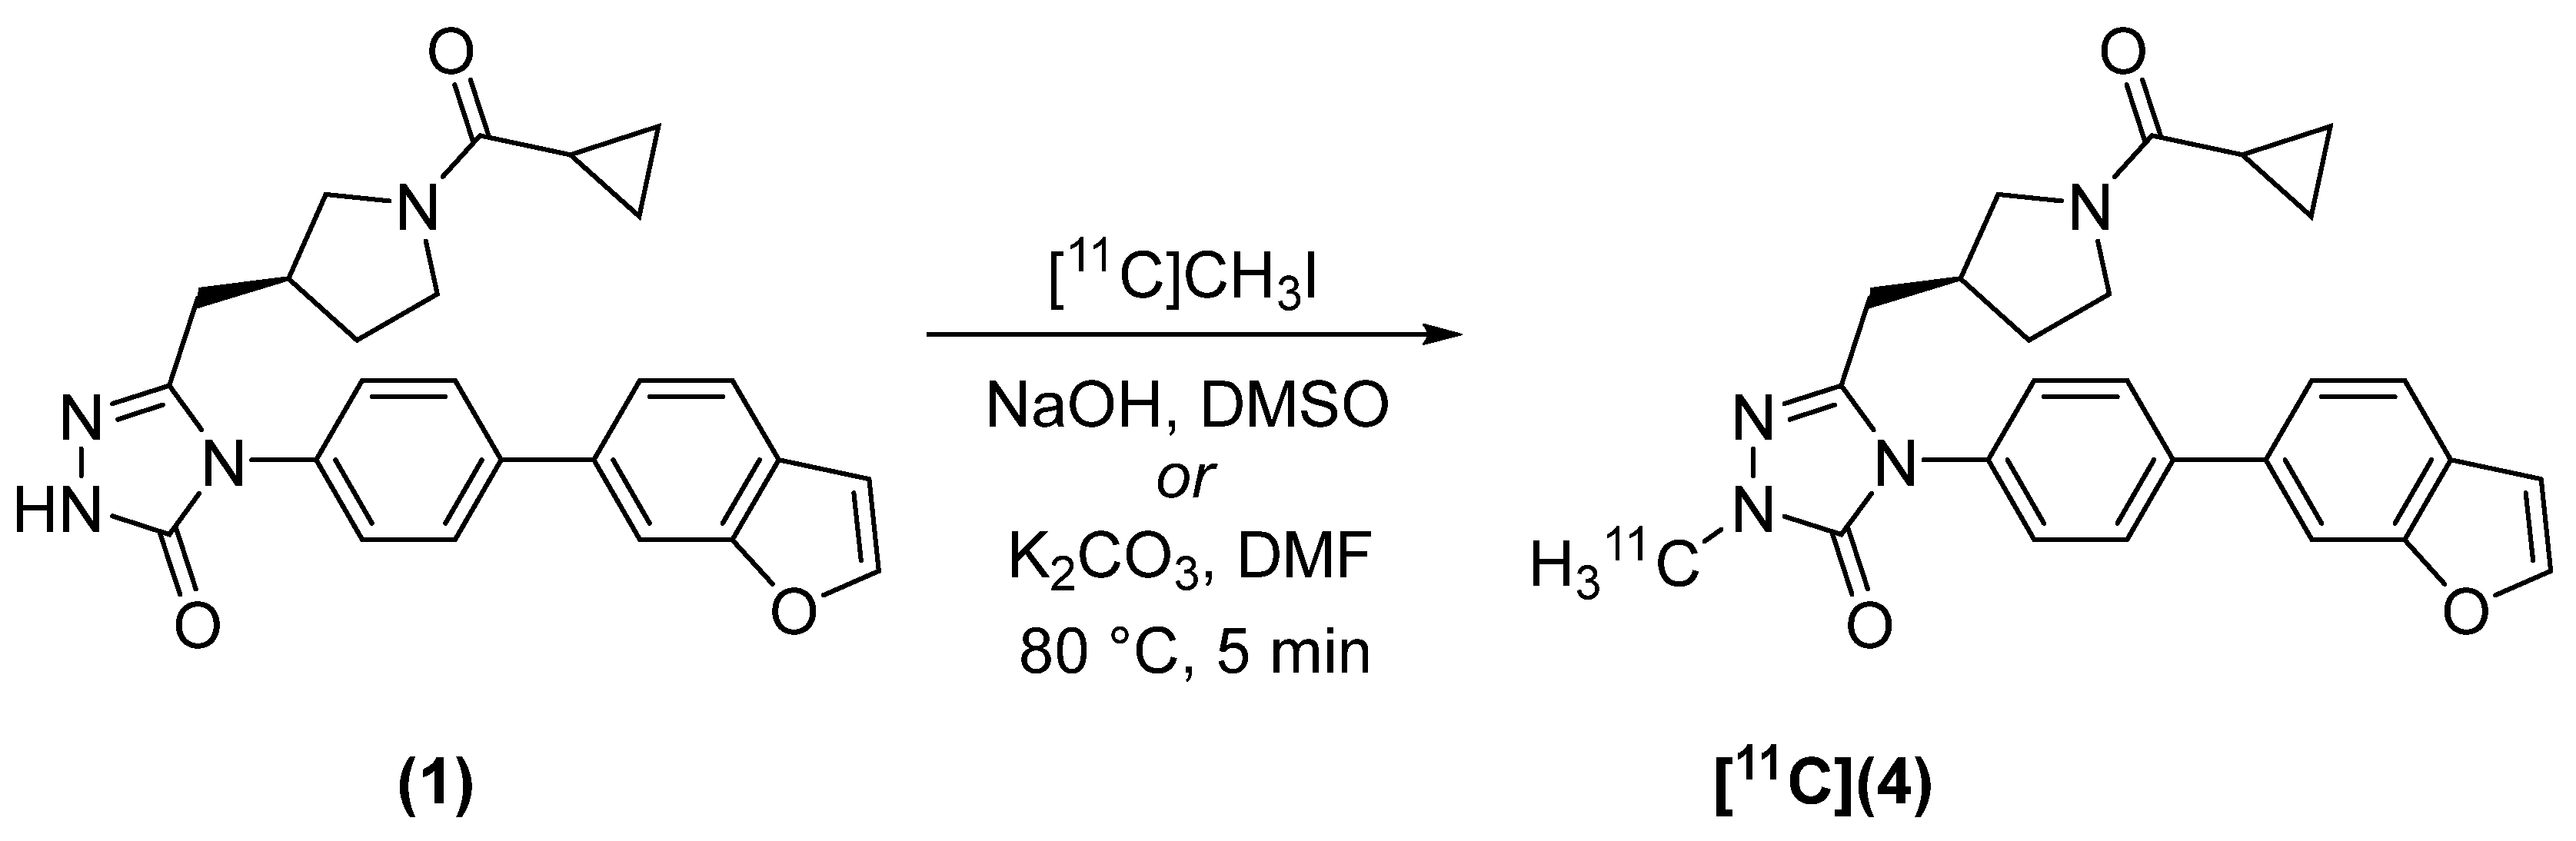

2.2. Radiosynthesis

4.2.1. (S)-4-(4-(benzofuran-6-yl)phenyl)-5-((1-(cyclopropanecarbonyl)pyrrolidin-3-yl)methyl)-2-[methyl-11C]-2,4-dihydro-3H-1,2,4-triazol-3-one ([11C]4)